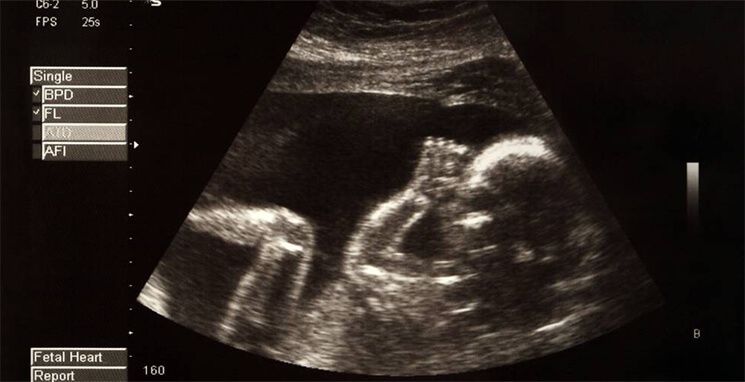

Kandungan Siti Sarah terpaksa digugurkan selepas disahkan oleh doktor. — Instagram/Shah Iskandar

Menggugurkan janin sebelum usia 120 hari diharuskan sekiranya mengancam nyawa ibu. — Gambar hiasan